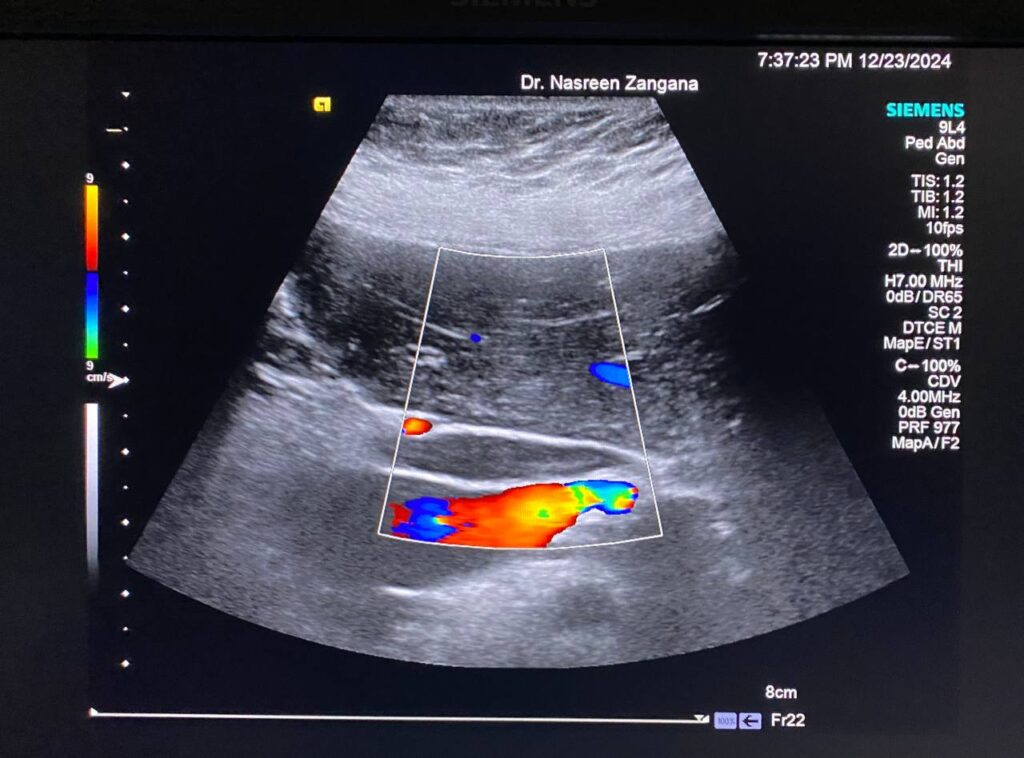

Diffuse dilated common bile duct 7.3mm , with presence of multiple echogenic foci within , the largest 3mm